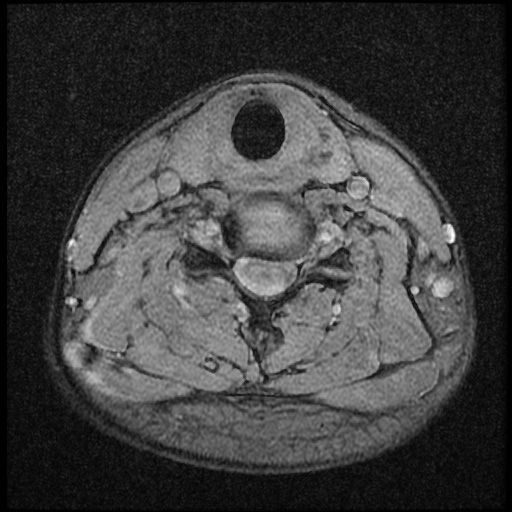

이 MRI 사진은 21년도 사고 당시 찍은 MRI 사진 입니다. 확인 부탁드립니다~

전체 mri를 다 봐여겠지만 보여주신 mri 컷에서는 의미있는 경추 디스크탈출이 보이지 않습니다.